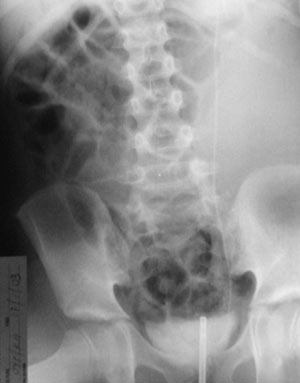

Το καλό ιστορικό και τα κλινικά ευρήματα συνηγορούσαν υπέρ της ύπαρξης ευμεγέθους

μετεγχειρητικού ουρινώματος αριστερά. Η διάγνωση επιβεβαιώθηκε και με υπερηχογράφημα

κοιλίας, όπου διακρίνεται καθαρά μεγάλη διάταση του πυελοκαλυκικού συστήματος

του αριστερού νεφρού και παρουσία μεγάλης ποσότητας υγρού, περιχαρακωμένο από

πεπαχυσμένη κάψα (εικόνα 4). Το ίδιο παρατηρείται και στην αξονική τομογραφία

άνω και κάτω κοιλίας (εικόνα 5).